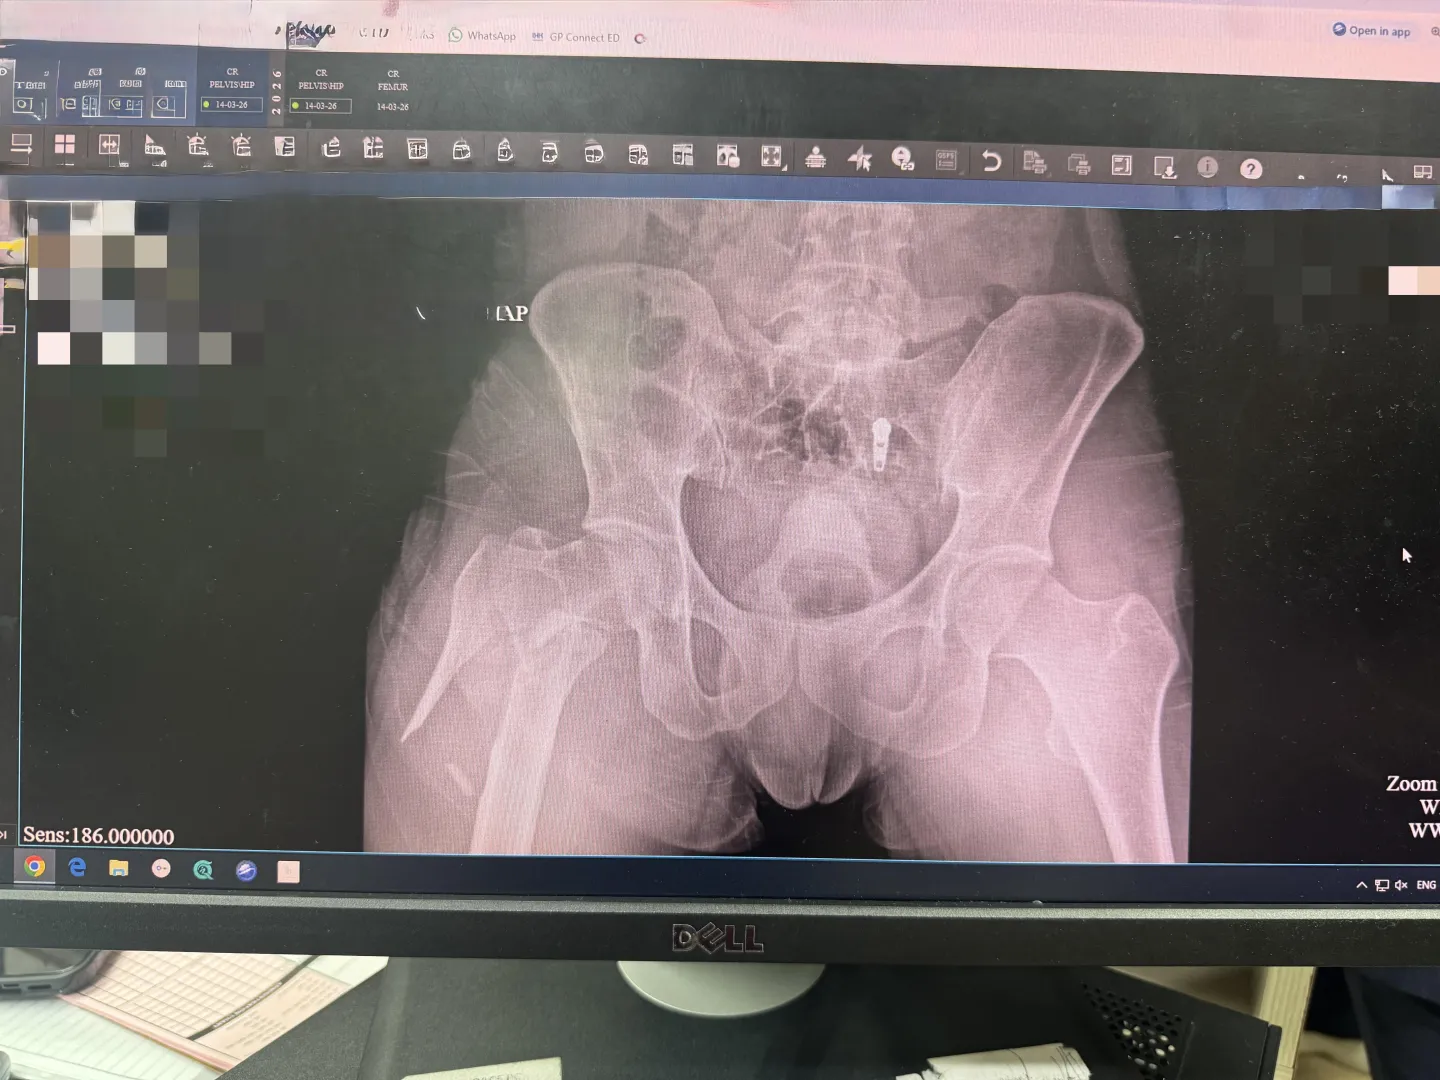

My right femur after slipping on wet floor at home.

My right femur after slipping on wet floor at home. posted by comedycord Previous Next